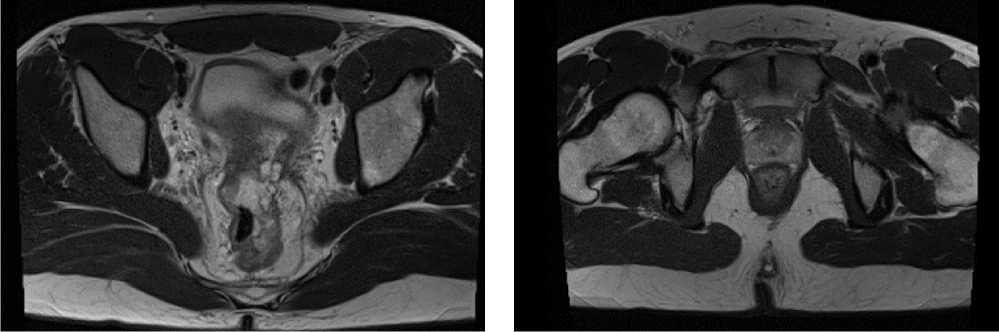

Клинический случай 3. Пациент Е., 37 лет. В июле 2022 г., в связи с дообследованием по поводу генеза кровянистых выделений из прямой кишки, выполнена ректороманоскопия, по результатам которой выявлено образование среднеампулярного отдела прямой кишки. По результатам гистологического исследования материала выявлена аденокарцинома толстой кишки, low grade.

При КТ органов брюшной полости и магнитно-резонансная томография (МРТ) органов малого таза (ОМТ) от августа 2022 г. визуализированы патологические образования в печени метастатического характера (n = 8), расположенные билобарно, и образование средне/верхнеампулярного отделов прямой кишки mrT3d/T4aN2 (CRM+ за счет прилежания лимфатического узла/EMVI+). По результатам молекулярно-генетического исследования обнаружена мутация G13D в 13 кодоне гена KRAS.

Диагноз был установлен как рак среднеампулярного отдела прямой кишки сТ4аN2M1 (hep).

По решению онкологического консилиума пациенту начат ПХТ 1 линии в режиме FOLFOX + бевацизумаб. С 02.09.2022 проведено 3 цикла ПХТ 1 линии, по результатам контрольных обследований зарегистрировано прогрессирование процесса за счет роста образований печени до 64 × 46 мм и появления линзовидного образования между передней поверхностью прямой кишки и задней поверхностью предстательной железы размерами 47 × 15 × 25 мм (рис. 7, 8).

Рис. 7. Результаты компьютерной томографии органов брюшной полости у пациента 37 лет с диагнозом метастатический колоректальный рак с признаками микросателлитной нестабильности (октябрь 2022 г., после 3-х циклов FOLFOX + бевацизумаб)

Fig. 7. Results of abdominal CT scan in a 37-year-old patient diagnosed with metastatic MSI-H colorectal cancer (October 2022, after 3 cycles of FOLFOX + bevacizumab)

Рис. 8. Результаты магнитно-резонансной томографии органов брюшной полости у пациента 37 лет с диагнозом метастатический колоректальный рак с признаками микросателлитной нестабильности (октябрь 2022 г., после 3-х циклов FOLFOX + бевацизумаб)

Fig. 8. Results of abdominal MRI in a 37-year-old patient diagnosed with metastatic MSI-H colorectal cancer (October 2022, after 3 cycles of FOLFOX + bevacizumab)

В октябре 2022 г. получены результаты иммуногистохимического исследования на предмет MSI, выявлена утрата ядерной экспрессии MLH1 и PMS2.

С учетом результатов ИГХ, прогрессирования процесса по результатам контрольных обследований, пациенту начата 2 линия системного лечения пембролизумабом в монорежиме.

С ноября 2022 г. выполнено 14 введений пембролизумаба с максимальным эффектом частичный регресс (образование между передней поверхностью прямой кишки и задней поверхностью предстательной железы регрессировало полностью). По результатам контрольных обследований (КТ ОБП и МРТ ОМТ от сентября 2023 г.) сохраняются очаги в печени до 21 × 11 мм, а также опухоль средне- и верхнеампулярного отделов прямой кишки с выраженным муцинозным компонентом. МР-стадия Т4а (CRM+, EMVI+) (рис. 9, 10).

Рис. 10. Частичный регресс, по данным магнитно-резонансной томографии органов брюшной полости, на фоне иммунотерапии пембролизумабом у пациента 38 лет с диагнозом метастатический колоректальный рак с признаками микросателлитной нестабильности; МР-стадия Т4а (CRM+, EMVI+) (сентябрь 2023 г.)

Fig. 10. Partial response according to abdominal magnetic resonance imaging during immunotherapy with pembrolizumab in a 38-year-old patient diagnosed with metastatic MSI-H colorectal cancer; MR stage T4a (CRM+, EMVI+) (September 2023)